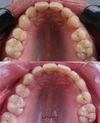

Diş Çapraşıklığı

Zirkonyum uygulamalar

Porselen uygulamaları

Laminate veneer